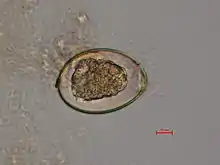

The adult worm is composed of three fairly distinct morphological segments: the scolex (head), the neck, and the lower body. Each side of the scolex has a slit-like groove, which is a bothrium for attachment to the intestine. The scolex attaches to the neck, or proliferative region. From the neck grow many proglottid segments which contain the reproductive organs of the worm. D. latum is the longest tapeworm in humans, averaging ten meters long. Unlike many other tapeworms, Diphyllobothrium eggs are typically unembryonated when passed in human feces.[4]

In adults, proglottids are wider than they are long (hence the name broad tapeworm). As in all pseudophyllid cestodes, the genital pores open midventrally.[5]